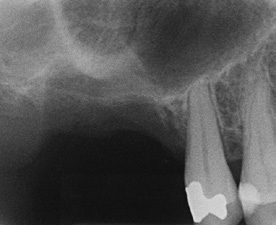

Die allgemeinmedizinisch gesunde Patientin befand sich aufgrund ihrer Grad-IV-Parodontitis seit 2013 in einem engmaschigen parodontalen Recall. Trotz der starken parodontalen Destruktion lagen stabile Verhältnisse vor. Ende 2016 stellte sich die Patientin mit Beschwerden an Zahn 16 vor. Dieser reagierte negativ auf die Sensibilitätsprobe und wies einen Furkationsgrad 3 auf. Zudem zeigte sich röntgenologisch eine apikale Aufhellungszone. Da bei dem Nachbarzahn 17 ebenfalls ein Furkationsgrad 3 bei einem Lockerungsgrad I vorlag, wurden in Absprache mit der Patientin Zahn 16 und 17 operativ entfernt. Die Patientin wünschte eine festsitzende, implantologisch-prothetische Rehabilitation und lehnte eine herausnehmbare Versorgung ab.

Nach einer Abheilzeit von 10 Wochen wurde im Rahmen der präimplantologischen Diagnostik aufgrund der Komplexität der Defektsituation im 1. Quadranten regio 16 und 17 neben der klinischen Untersuchung eine DVT-Aufnahme angefertigt. Es zeigte sich ein transversaler und vertikaler Knochendefekt mit einer Restknochenhöhe von teilweise nur 1 mm. Zu beachten war auch die Höhe des Knochenlagers, das sich teilweise auf Höhe des Apex des Nachbarzahnes 15 befand (Abb. 1a und b). Dieser dreidimensionale Defekt sollte durch einen externen Sinuslift nach kranial sowie eine ventrale horizontale auflagernde Augmentation ausgeglichen werden. Hierfür wurde mit dem DICOM-Datensatz der DVT-Aufnahme ein virtuelles Modell hergestellt, welches die Planungsgrundlage für das Augmentationsvolumen darstellte (Abb. 1c). Anhand dieser Daten und in Abstimmung mit dem Behandler stellte die ReOss GmbH ein patientenindividuell gedrucktes Titangitter für die Augmentation her.